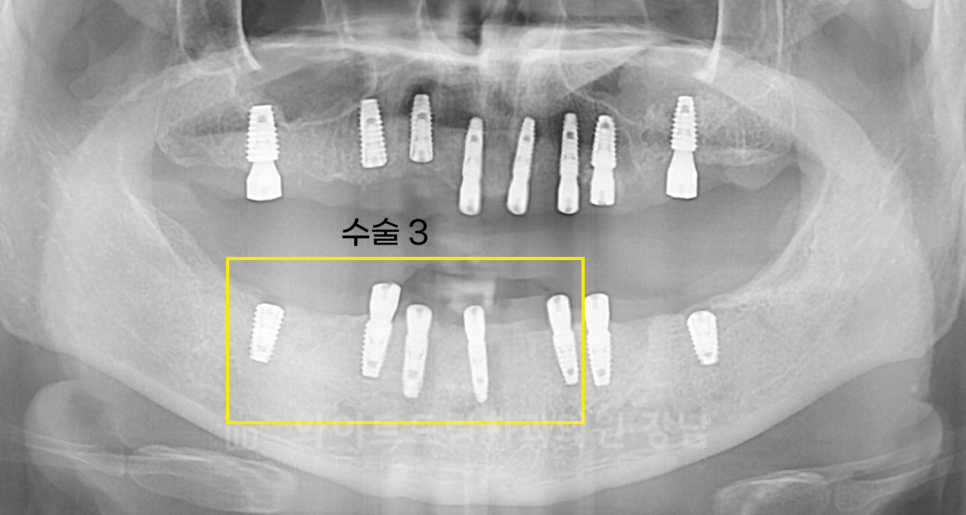

수술 3) 30, 40번대 임플란트 수술 (20.05.02)

수술 3을 마지막으로 전악 발치 + 임플란트 식립이 완료되었습니다.

이제, 잇몸뼈와 임플란트가 단단하게 유착할 수 있는 회복 기간이 필요합니다.

이 기간에는 빨대 사용 금지, 흡연/음주 등을 하시면 안 되는 주의사항만 잘 지켜주신다면 된답니다.

환자분은 4개월의 회복 기간을 두고, 잇몸뼈와 임플란트가 단단히 유착됨을 확인한 후

임플란트 보철 제작을 위한 2차 수술 + 인상채득에 들어갔습니다.